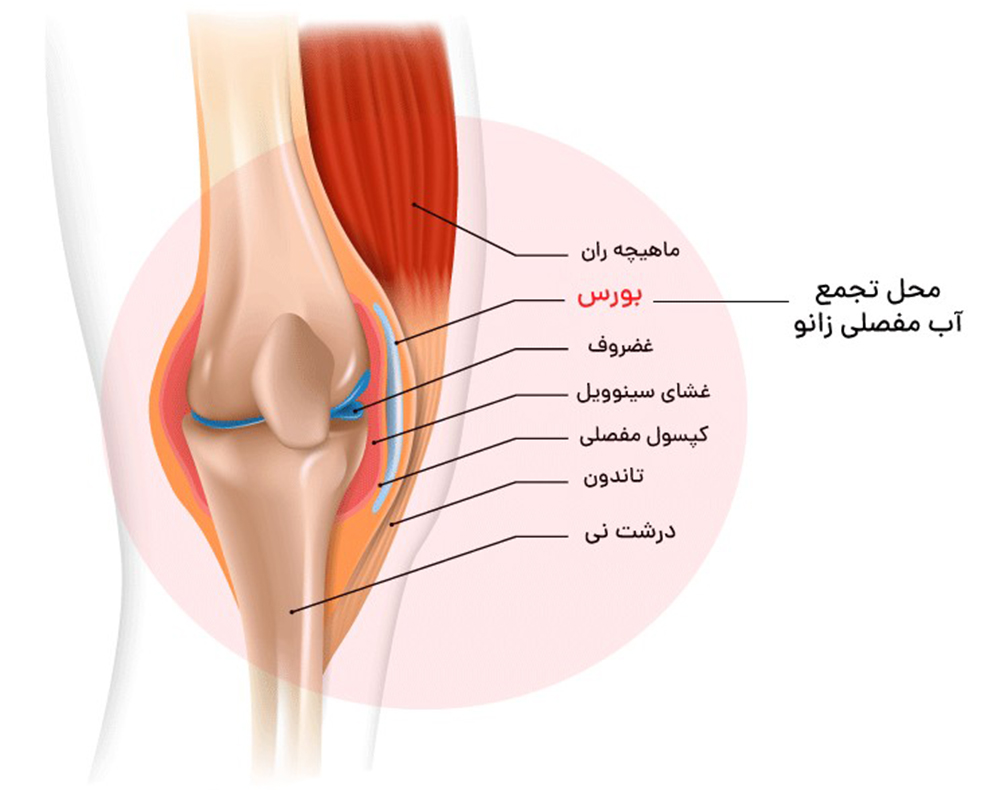

این مشکل معمولاً ناشی از ناپایداری مفصل زانو، ضعف عضلات اطراف مفصل یا آسیب ساختارهای داخلی زانو است.

4. پارگی مینیسک، سینوویت و آرتریت

- التهاب غشای مفصل (سینوویت)

- آرتریت یا التهاب مفصلی

- میتوانند باعث درد، تورم و کاهش ثبات زانو شوند و در نهایت خالی کردن زانو را ایجاد کنند.

ساییدگی غضروف به دلیل افزایش سن، فشار بیشازحد یا آرتروز زانو رخ میدهد. با تخریب غضروف، حرکت مفصل روانی خود را از دست داده و ناپایداری ایجاد میشود.